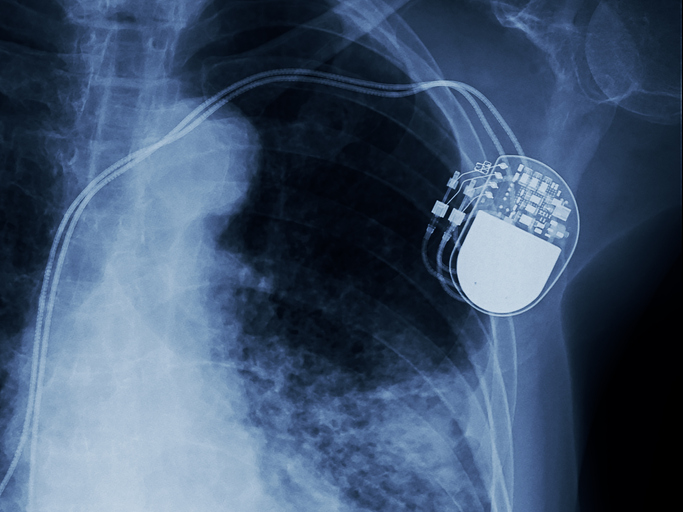

Herzschrittmacher: Ein Gerät mit Komplikationen

Ein Herzschrittmacher ist ein Gerät, das elektrische Impulse an das Herz sendet, um den normalen Herzrhythmus aufrechtzuerhalten.

Während dies für einige Patienten geeignet sein kann, ist es keine dauerhafte Lösung für alle und erfordert regelmäßige Überwachung und möglicherweise Anpassungen.

Zudem bestehen nach einer Herzschrittmacher-Implantation Risiken. Hierzu zählen Blutungen, die Bildung eines Blutgerinnsels oder auch Nervenverletzungen.

“Betroffene erhalten nach der Operation einen Herzschrittmacherausweis. Diesen sollten sie immer bei sich tragen und zum Beispiel bei Kontrollen am Flughafen vorzeigen. Die Metalldetektoren erfassen Schrittmacher und geben ein Signal ab.”